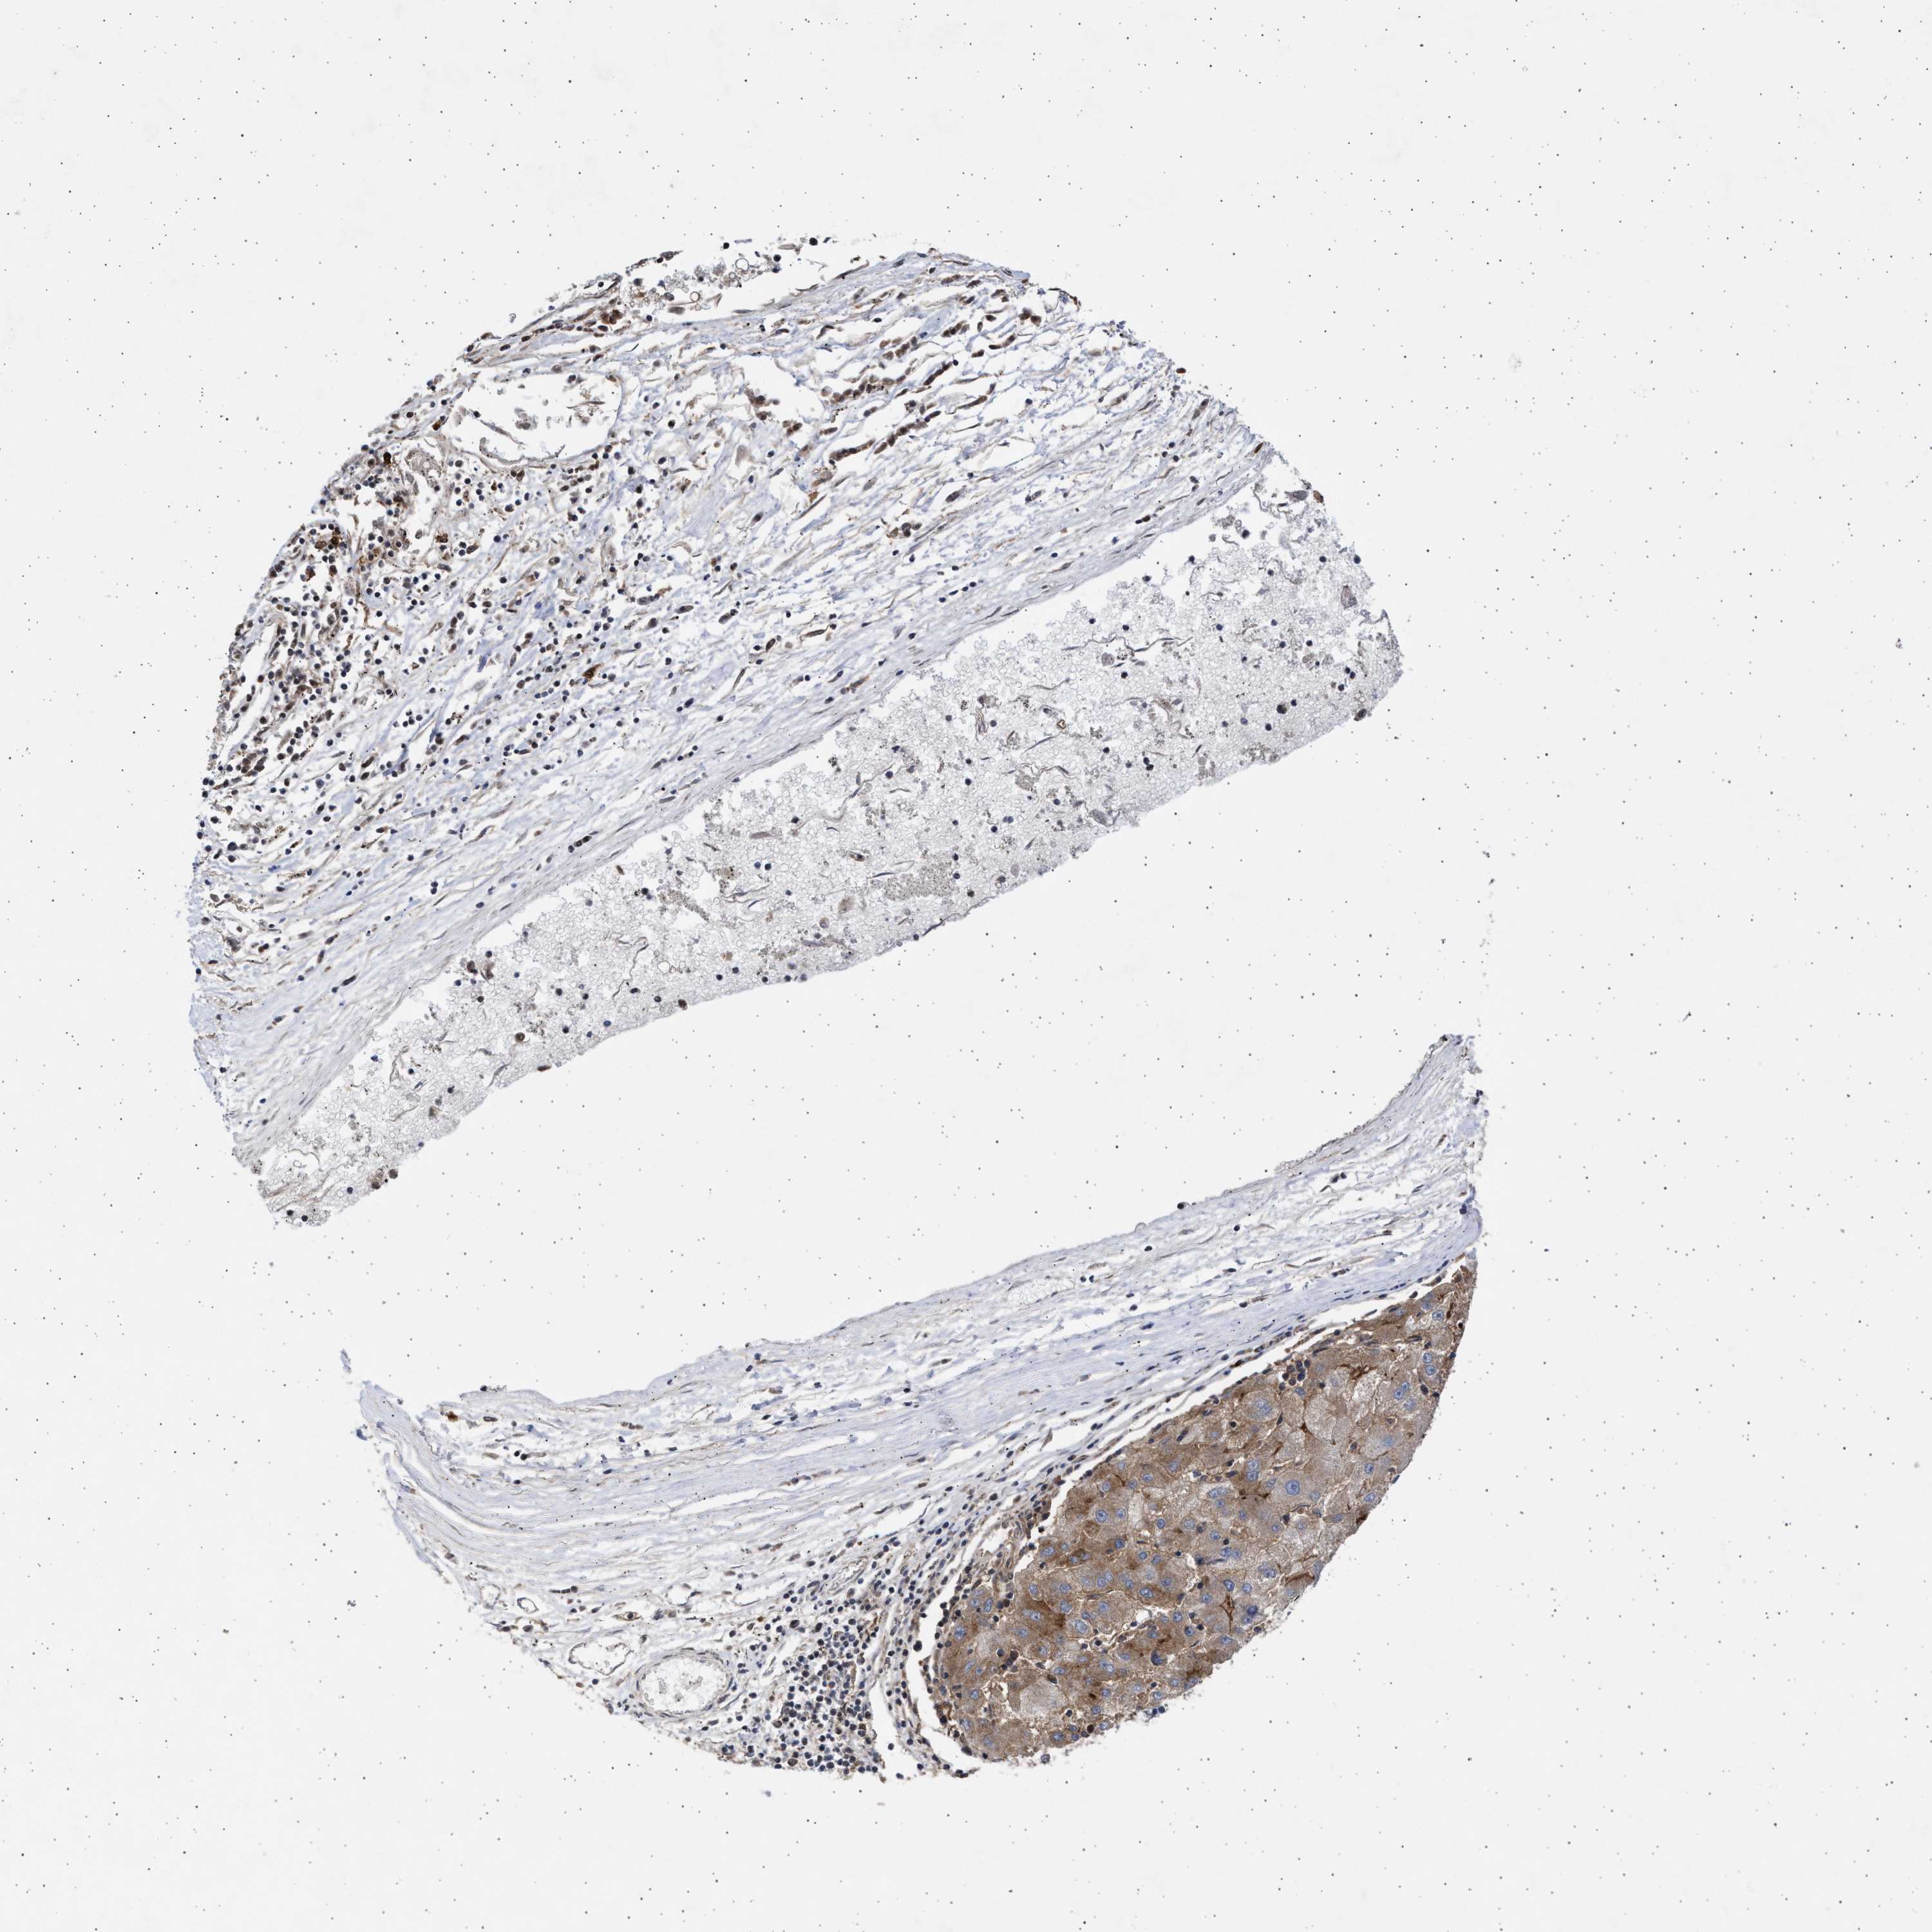

LIVER CANCER - Protein expressioni

A mouse-over function shows sample information and annotation data. Click on an image to view it in a full screen mode. Samples can be filtered based on level of antibody staining by selecting one or several of the following categories: high, medium, low and not detected. The assay and annotation is described here.

Antibody stainingi

Antibody staining in the annotated cell types in the current human tissue is reported as not detected, low, medium, or high, based on conventional immunohistochemistry profiling in selected tissues. This score is based on the combination of the staining intensity and fraction of stained cells.

Each image is clickable and will lead to virtual microscopy that enables deeper exploration of all samples and also displays staining intensity scores, fraction scores and subcellular localization as well as patient and tissue information for each sample.

Antibody HPA023010

Antibody HPA052380

Staining

High

Medium

Low

Not detected

Intensity

Strong

Moderate

Weak

Negative

Quantity

>75%

75%-25%

<25%

None

Location

Nuclear

Cytoplasmic/membranous

Cytoplasmic/membranous,nuclear

Cholangiocarcinoma

Carcinoma, Hepatocellular, NOS